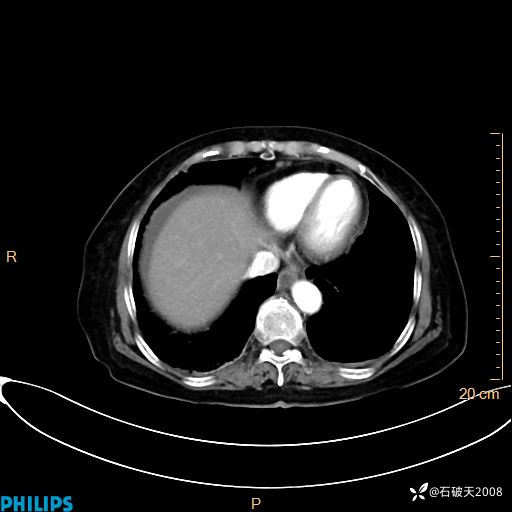

平扫

动脉期

MIP

静脉期